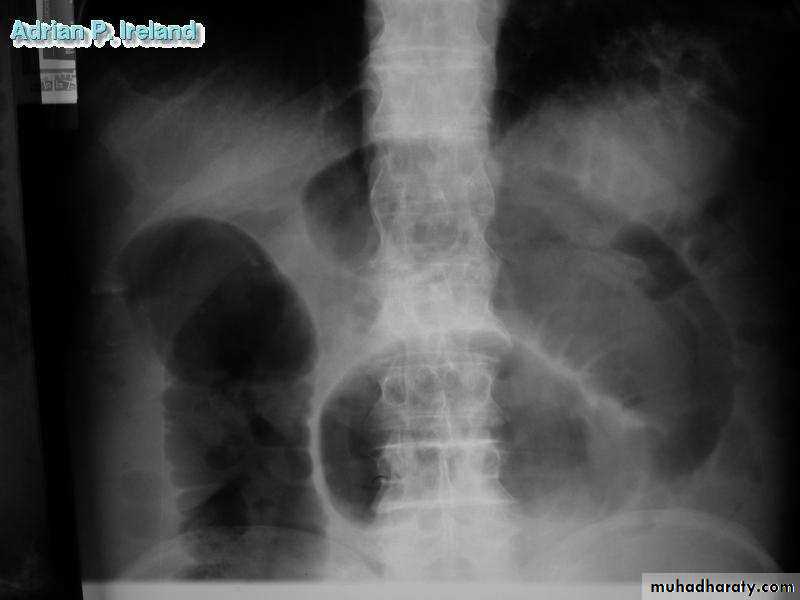

• Radiology, Small bowel obstruction

• Operative Findings; Small bowel obstruction